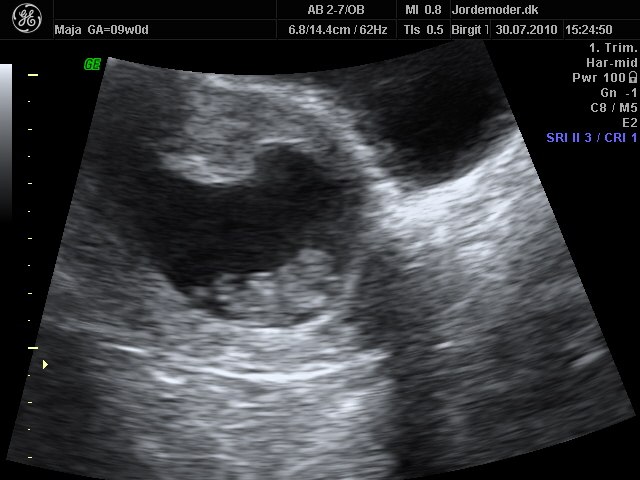

Sætter lige et billede ind fra vores scanning i 9+0 så du kan se hvordan det ser ud, omkring det tidpsunkt

Vedhæftede fotos (klik for at se i fuld størrelse)